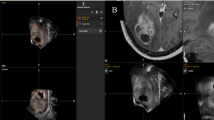

a Craniotomy planning using the navigated US probe; a1 US probe is used like a neuro-navigator pointer; a2 screenshot of the VN unit: in the superior right box, it is visualized the MRI corresponding to the probe orientation; the superior left box usually displays the US imaging that it is not visualized because of bone shielding, the inferior boxes depict different orthogonal planes. b intraoperative procedure, bone flap has been removed, and trans-dural US scan is performed; b1 US probe is approached to dura mater, to perform a two-axis B-mode evaluation of the lesion and a first comparison between iUS and preoperative MRI; b2 screenshot of the VN unit: in the superior right box, it is visualized the MRI corresponding to the probe orientation; the superior left box displays the US imaging; the inferior boxes depict different orthogonal planes

At this point, a first fine-tuning registration phase is performed. The brain surface is scanned with standard B-mode US modality, and the lesion is analyzed: on the screen of the virtual navigation system, the US imaging and the correspondent preoperative MRI are displayed merged together (Fig. 1b). Thanks to this feature, it is possible to evaluate the accuracy of the first registration procedure looking for misalignment of major anatomical structures such as ventricles, arteries, mid-brain and dural structures between the MR image and the real-time US image. If a difference between the real position of a structure (assessed by US image) and the virtual position (according to the virtual navigation system) is observed, the error is measured and might be corrected in two ways (Fig. 3):